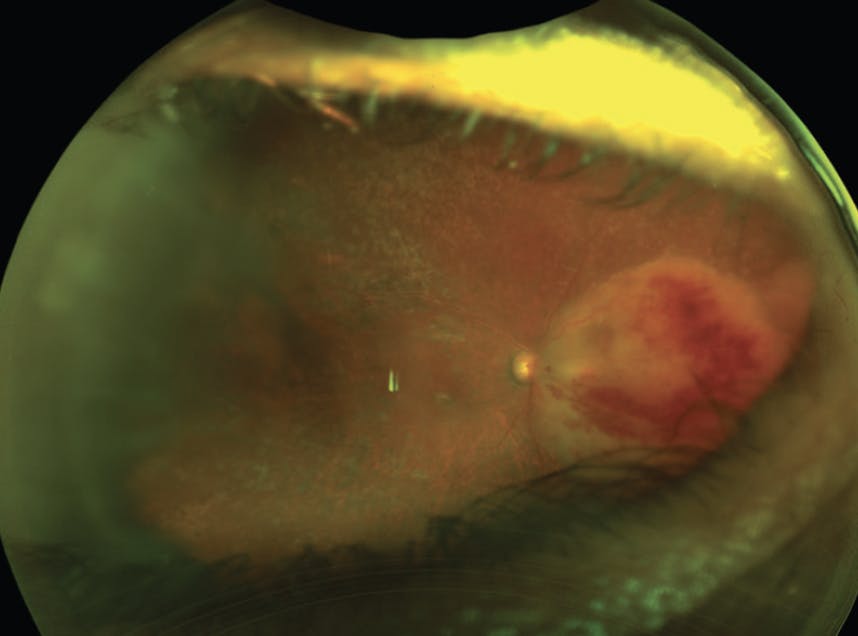

Vitrectomy is also a helpful adjunct when managing the sequela of intraocular inflammation. Complications of inflammation include vitreous debris, retinal detachment, epiretinal membrane, and macular holes. A vitrectomy can remove visually significant vitreous debris, alleviate traction, and identify pathology often blocked by vitritis. When approaching retinal detachments, it is important to counsel patients on the higher rate of redetachment compared with traditional retinal detachment surgery. A few reports have evaluated retinal reattachment rates after infectious retinitis, with primary reattachment rates of about 60%.16 Additionally, patients may more often require silicone oil, which can have antimicrobial properties and provide an effective tamponade (Figure 4).

<p>Figure 4. A 52-year-old man presented with retinal whitening and vitreous haze (A). Acute retinal necrosis was suspected and PCR testing was positive for herpes simplex virus. The patient initially received intravitreal antivirals and responded, but later developed a combined tractional and rhegmatogenous retinal detachment that required vitrectomy and silicone oil (B).<br />

Image courtesy of Steven Yeh, MD</p>

Figure 4. A 52-year-old man presented with retinal whitening and vitreous haze (A). Acute retinal necrosis was suspected and PCR testing was positive for herpes simplex virus. The patient initially received intravitreal antivirals and responded, but later developed a combined tractional and rhegmatogenous retinal detachment that required vitrectomy and silicone oil (B).

Image courtesy of Steven Yeh, MD